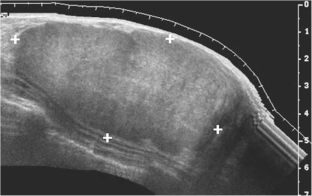

Breast tissue undergoes a series of changes from birth to puberty. The majority of the changes are transient, related to physiological hormonal changes. Although the breast is identical in both sexes at birth, its histology and development will eventually differ. It is important for radiologists to have a basic understanding of endocrinological changes and appearance on imaging to avoid potential pitfalls, particularly on ultrasound, which is the primary modality used to evaluate the breast.